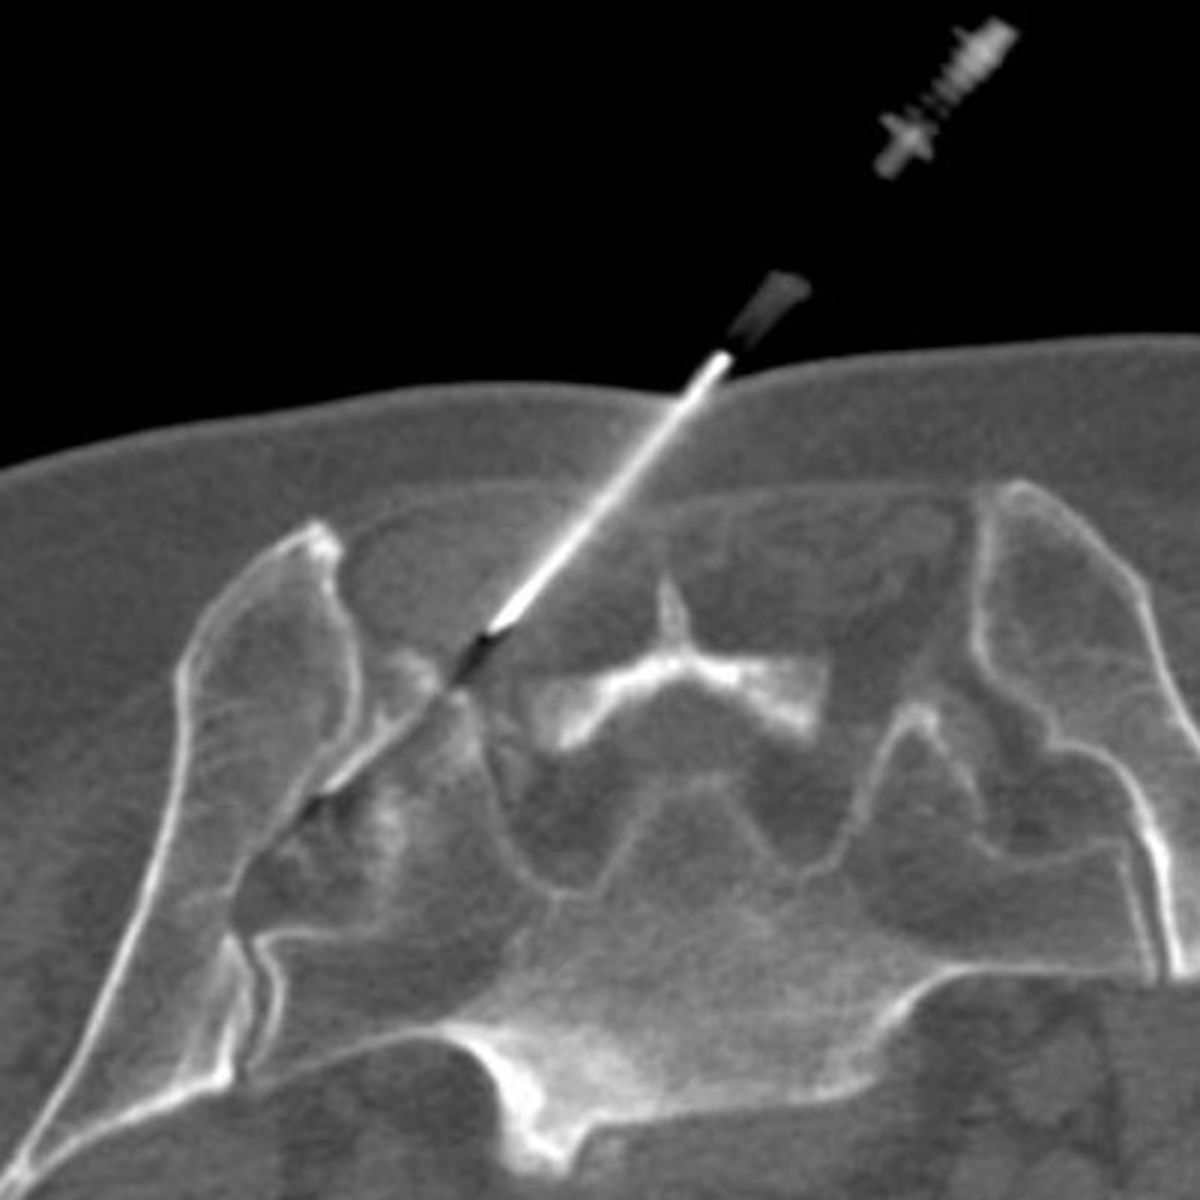

Zur Therapie stehen unsere modernen Großgeräte wie Computertomographen und Durchleuchtungsgeräte (Zwei-Ebenen-Angiographie) zur Verfügung, die schonendes und präzises Arbeiten im Millimeterbereich gewährleisten, was der Sicherheit und der Verbesserung der klinischen Ergebnisse für unsere PatientInnen dient.

- Minimalinvasive CT-gesteuerte Schmerztherapien

- Periradikuläre Therapie